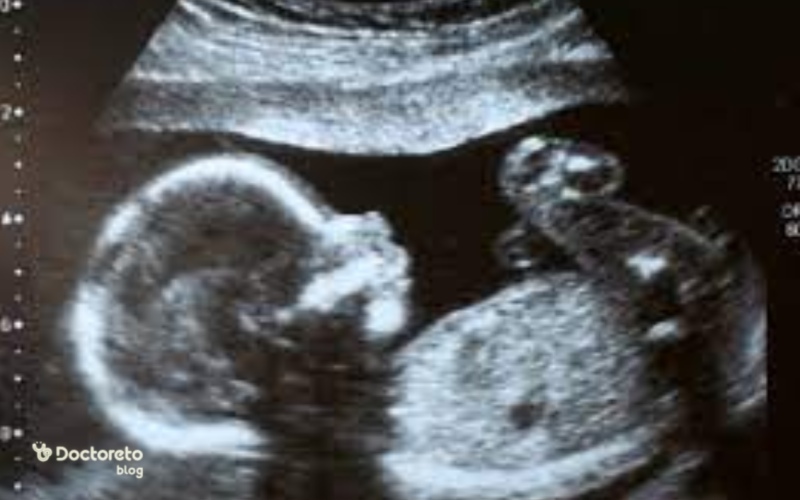

وضعیت جنین در هفته بیستم بارداری

در هفته ۲۰ بارداری جنین در سونوگرافی از سر تا باسن اندازه گرفته میشود. اگر بخواهیم از سر تا نوک پا را اندازه بگیریم، قد جنین در این هفته به ۲۸ سانتیمتر میرسد و تغییرات زیر در هفته ۲۰ حاملگی اتفاق میافتد:

جنین 20 هفته چه شکلی است؟

جنین در این هفته تقریبا اندازه یک موز است. وزن جنین هم تقریبا ۳۳۰ گرم است. اگر میخواهید وزن جنین را بدانید، تقریبا برابر با وزن سه سیب متوسط است. جنین در هفته بیستم حاملگی با لایه سفید ورنیکس پوشیده شده است. جنین بسیار فعال شده و در رحم انگشت شست خود را میمکد.

سونوگرافی هفته بیستم بارداری

اگر هفته قبل سونوگرافی انجام ندادهاید، در این هفته لازم است سونوگرافی سهماهه دوم بارداری انجام شود. به این آزمایش، سونوگرافی سطح ۲، سونوگرافی ساختاری یا اسکن آناتومی میگویند. در این تست باید رشد اعضای بدن و تمامی اندامهای جنین بررسی شود. بند ناف، جفت و مایع آمنیوتیک نیز ارزیابی میشوند. اگر جنین در موقعیت مناسب قرار گرفته باشد، میتوان جنسیت را نیز در این هفته متوجه شد.